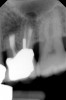

Clinical procedure: If apical bone loss is present (Figure 1) a collagen/gelatin sponge (eg, Gelfoam®, Pfizer Inc., www.pfizer.com) can be placed apically so that the MTA can be delivered to the desired working length. (Any other surgical resorbable sponge would also work, such as OraPlug® [Salvin Dental Specialties, www.salvin.com], Surgifoam® [Midwest Dental, www.mwdental.com], or Surgispon® [Aegis Lifesciences, www.surgispon.com]). This is done by taking a small piece (2 mm x 2 mm) of the resorbable sponge and pushing it down to and through the root apex with an endodontic file. Once this is done, MTA is packed down the canal with a custom-fitted cone. The clinician can use a rubber stopper on the gutta-percha cone to know the exact length of MTA placed in the apical third (Figure 2). Once the apical third is sealed with 3 mm to 5 mm of MTA, the remaining coronal canal space can be back-filled using a warm gutta-percha technique (Figure 3).